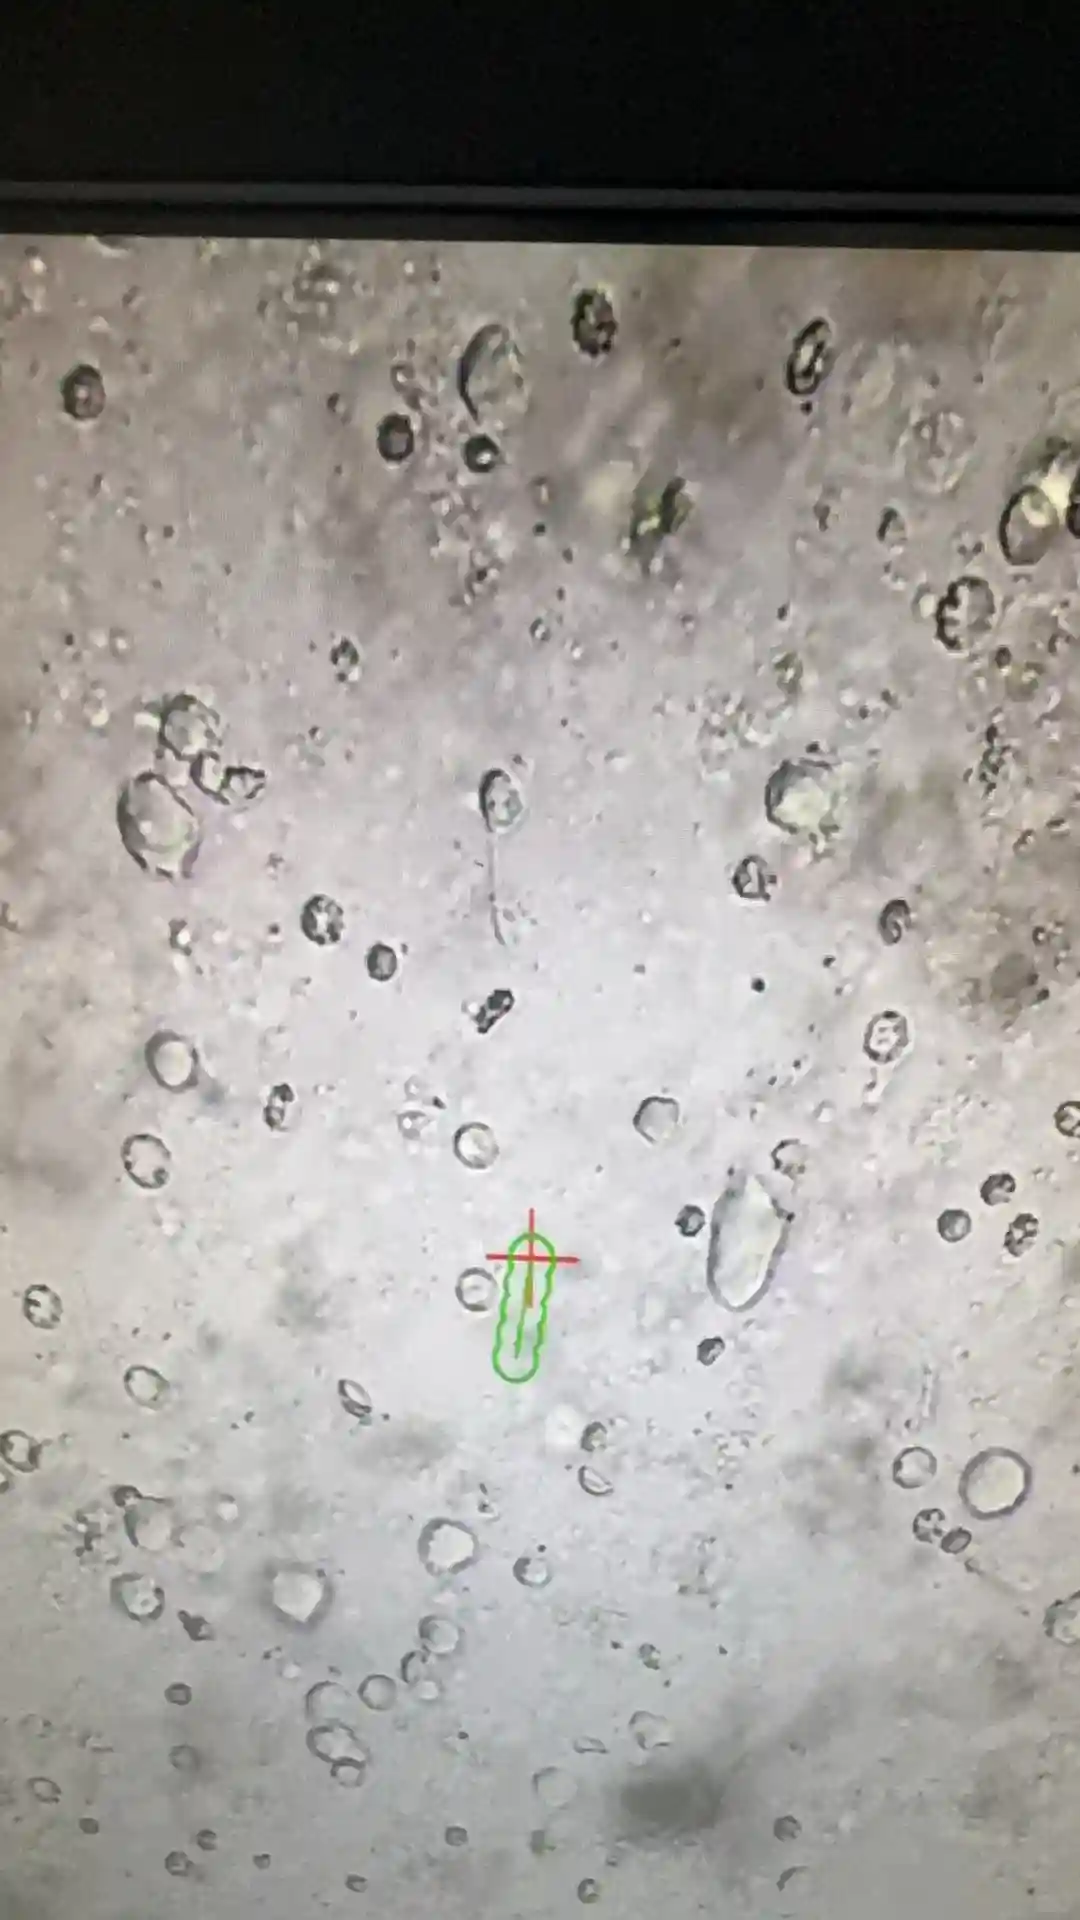

#无精症 #切开取精

#无精症 #切开取精 种宝宝的第4天好种子都回向给想好孕的你 供卵小孩健康吗